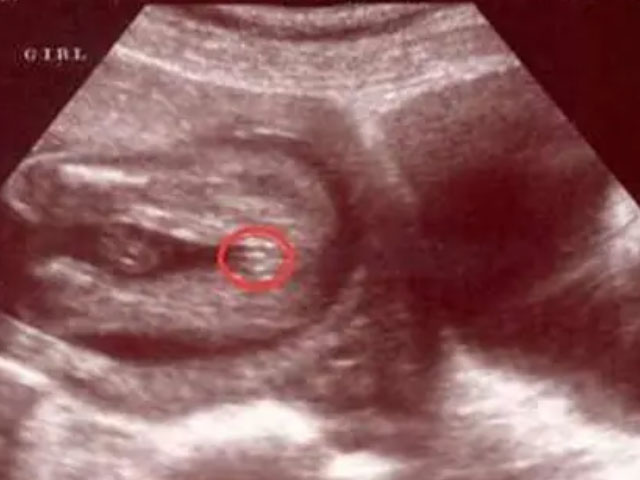

1. 可以看胎儿双腿之间,如果说这个部位是有三条白线,而且呈小凹槽状、圆圆的,大概率怀的是女孩,如果是凸出的东西,大概率是男孩;

4. 你还可以观察四维彩超单的结果,如果是双侧肾盂明显分离,表示是男孩,如果是双侧肾盂没有明显分开,就是女孩;